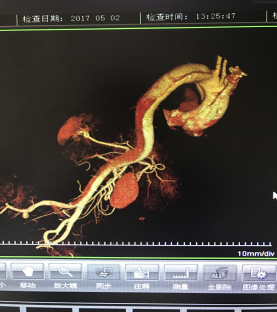

5月2號劉大伯照常早起干活,突然胸部劇烈疼痛,難以忍受,全身大汗,同時伴有右上肢發(fā)涼,他心想這次心絞痛比之前嚴(yán)重的多啊,趕緊叫上孩子到吉林國文醫(yī)院心血管內(nèi)科住院,患者長期高血壓病史,血壓一直控制不理想,大夫給他做了檢查,測左上肢血壓:82/45mmHg,右上肢血壓測不出,心率52次/分,右側(cè)肱動脈、尺動脈、橈動脈搏動消失,左側(cè)股動脈搏動較右側(cè)弱?!霸懔耍p側(cè)血壓差別這么大,是不是主動脈夾層了?”,接診大夫趕緊找來李主任,李主任反復(fù)詢問患者病情,表情突然凝重起來,患者胸痛這么明顯,血壓低的厲害,主動脈夾層的可能性很大。二話不說,李主任立即聯(lián)系影像科的醫(yī)生準(zhǔn)備做主動脈CTA,移動患者做檢查的過程大夫們非常小心,嚴(yán)密監(jiān)測患者血壓變化情況。兩個小時后結(jié)果出來了,主動脈夾層從升主動脈一直撕裂到左側(cè)髂總動脈?。?!

李主任詳細(xì)的與劉大伯的女兒交代了病情,手術(shù)是挽救生命的唯一辦法,為了劉大伯的一線生機(jī),我們積極聯(lián)系了我省權(quán)威的心血管外科,并做了詳細(xì)的匯報,兩家醫(yī)院對此非常重視,為劉大伯開通了綠色通道,安全的把他總到上級醫(yī)院,當(dāng)天便給他進(jìn)行血管置換及覆膜支架植術(shù)。他術(shù)后恢復(fù)的很好,后來劉大伯的女兒看望我們,感嘆道:沒想到國文醫(yī)院心內(nèi)科應(yīng)急能力這么高,在那么短的時間內(nèi)診斷明確,才給了我的老父親手術(shù)的機(jī)會。